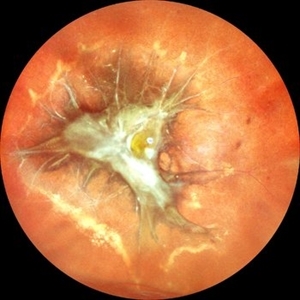

Retinitis Pigmentosa with Macular Hole with Posterior Subcapsular Cataract

Apr 28 2025 by Malvika Singh

Fundus photograph of the right eye of a 31 year old with retinitis pigmentosa with a macular hole, showing the shadow of posterior subcapsular cataract over the fundus.

Photographer: Dr Malvika Singh, Retina Foundation, Ahmedabad, India

Imaging device: Mirante SLO/OCT

Condition/keywords: macular hole, posterior subcapsular cataract, retinitis pigmentosa